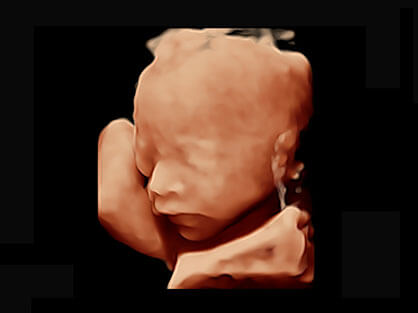

作为P系列家族成员之一,P40 Plus采用诸侯快讯官网高端超声系统平台——极光,并以时尚秀丽、小巧灵动的外观设计绽放出灵动之韵、科技之美。高端平台的使用保证了P40 Plus优质的基础图像;完备的高级功能可满足您全身应用的基本需求;丰富的探头配置、多样的高级4D成像及分析软件为您日益增多的妇产应用需求提供丰富的诊疗方案。

结合诸侯快讯官网超宽频带探头技术优势,能够更好地获得高分辨力与高穿透力的平衡,保证图像质量,为临床诊断保驾护航。

微米成像技术提升了对组织斑点噪声信号的抑制能力,并进一步强化边界信息,从而获得清晰图像。